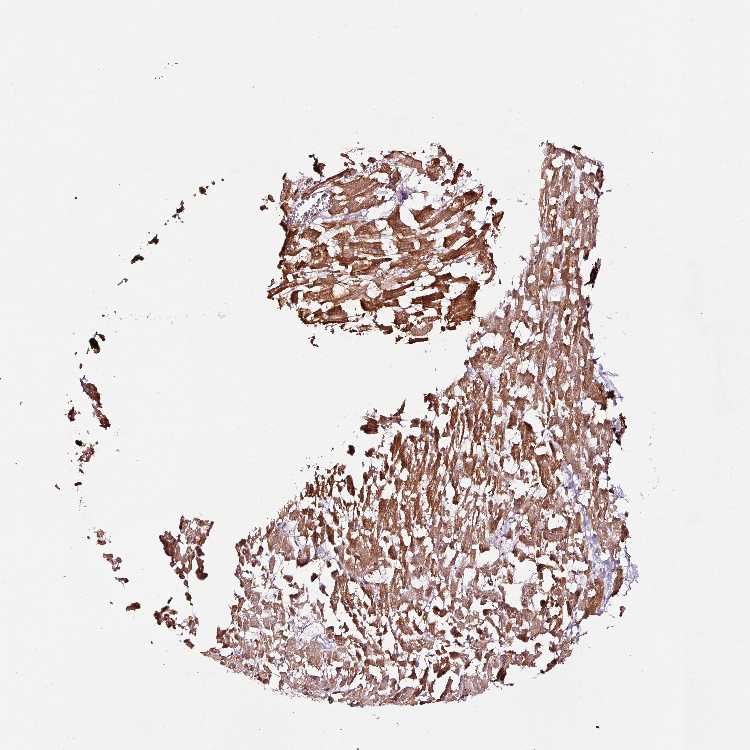

HEART MUSCLE - Antibody stainingi

Antibody staining in the annotated cell types in the current human tissue is reported as not detected, low, medium, or high, based on conventional immunohistochemistry profiling in selected tissues. This score is based on the combination of the staining intensity and fraction of stained cells.

Each image is clickable and will lead to virtual microscopy that enables deeper exploration of all samples and also displays staining intensity scores, fraction scores and subcellular localization as well as patient and tissue information for each sample.

Antibody HPA047089Antibody HPA053624

Cardiomyocytes HighHigh